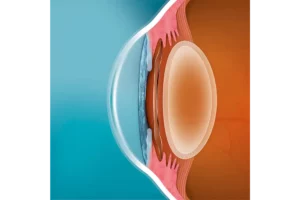

- EVO ICL is een phake lens.

- EVO wordt direct achter de iris en vóór de natuurlijke kristallijne lens geplaatst.

- De toevoeging van de centrale aqua port bij EVO vergemakkelijkt de stroom van aqueous humor doorheen de lens.

- De EVO ICL-procedure vereist geen verwijdering van corneaweefsel.

- De EVO-lens is een reversibel implantaat.

- Behoudt zowel cornea als natuurlijke lens3